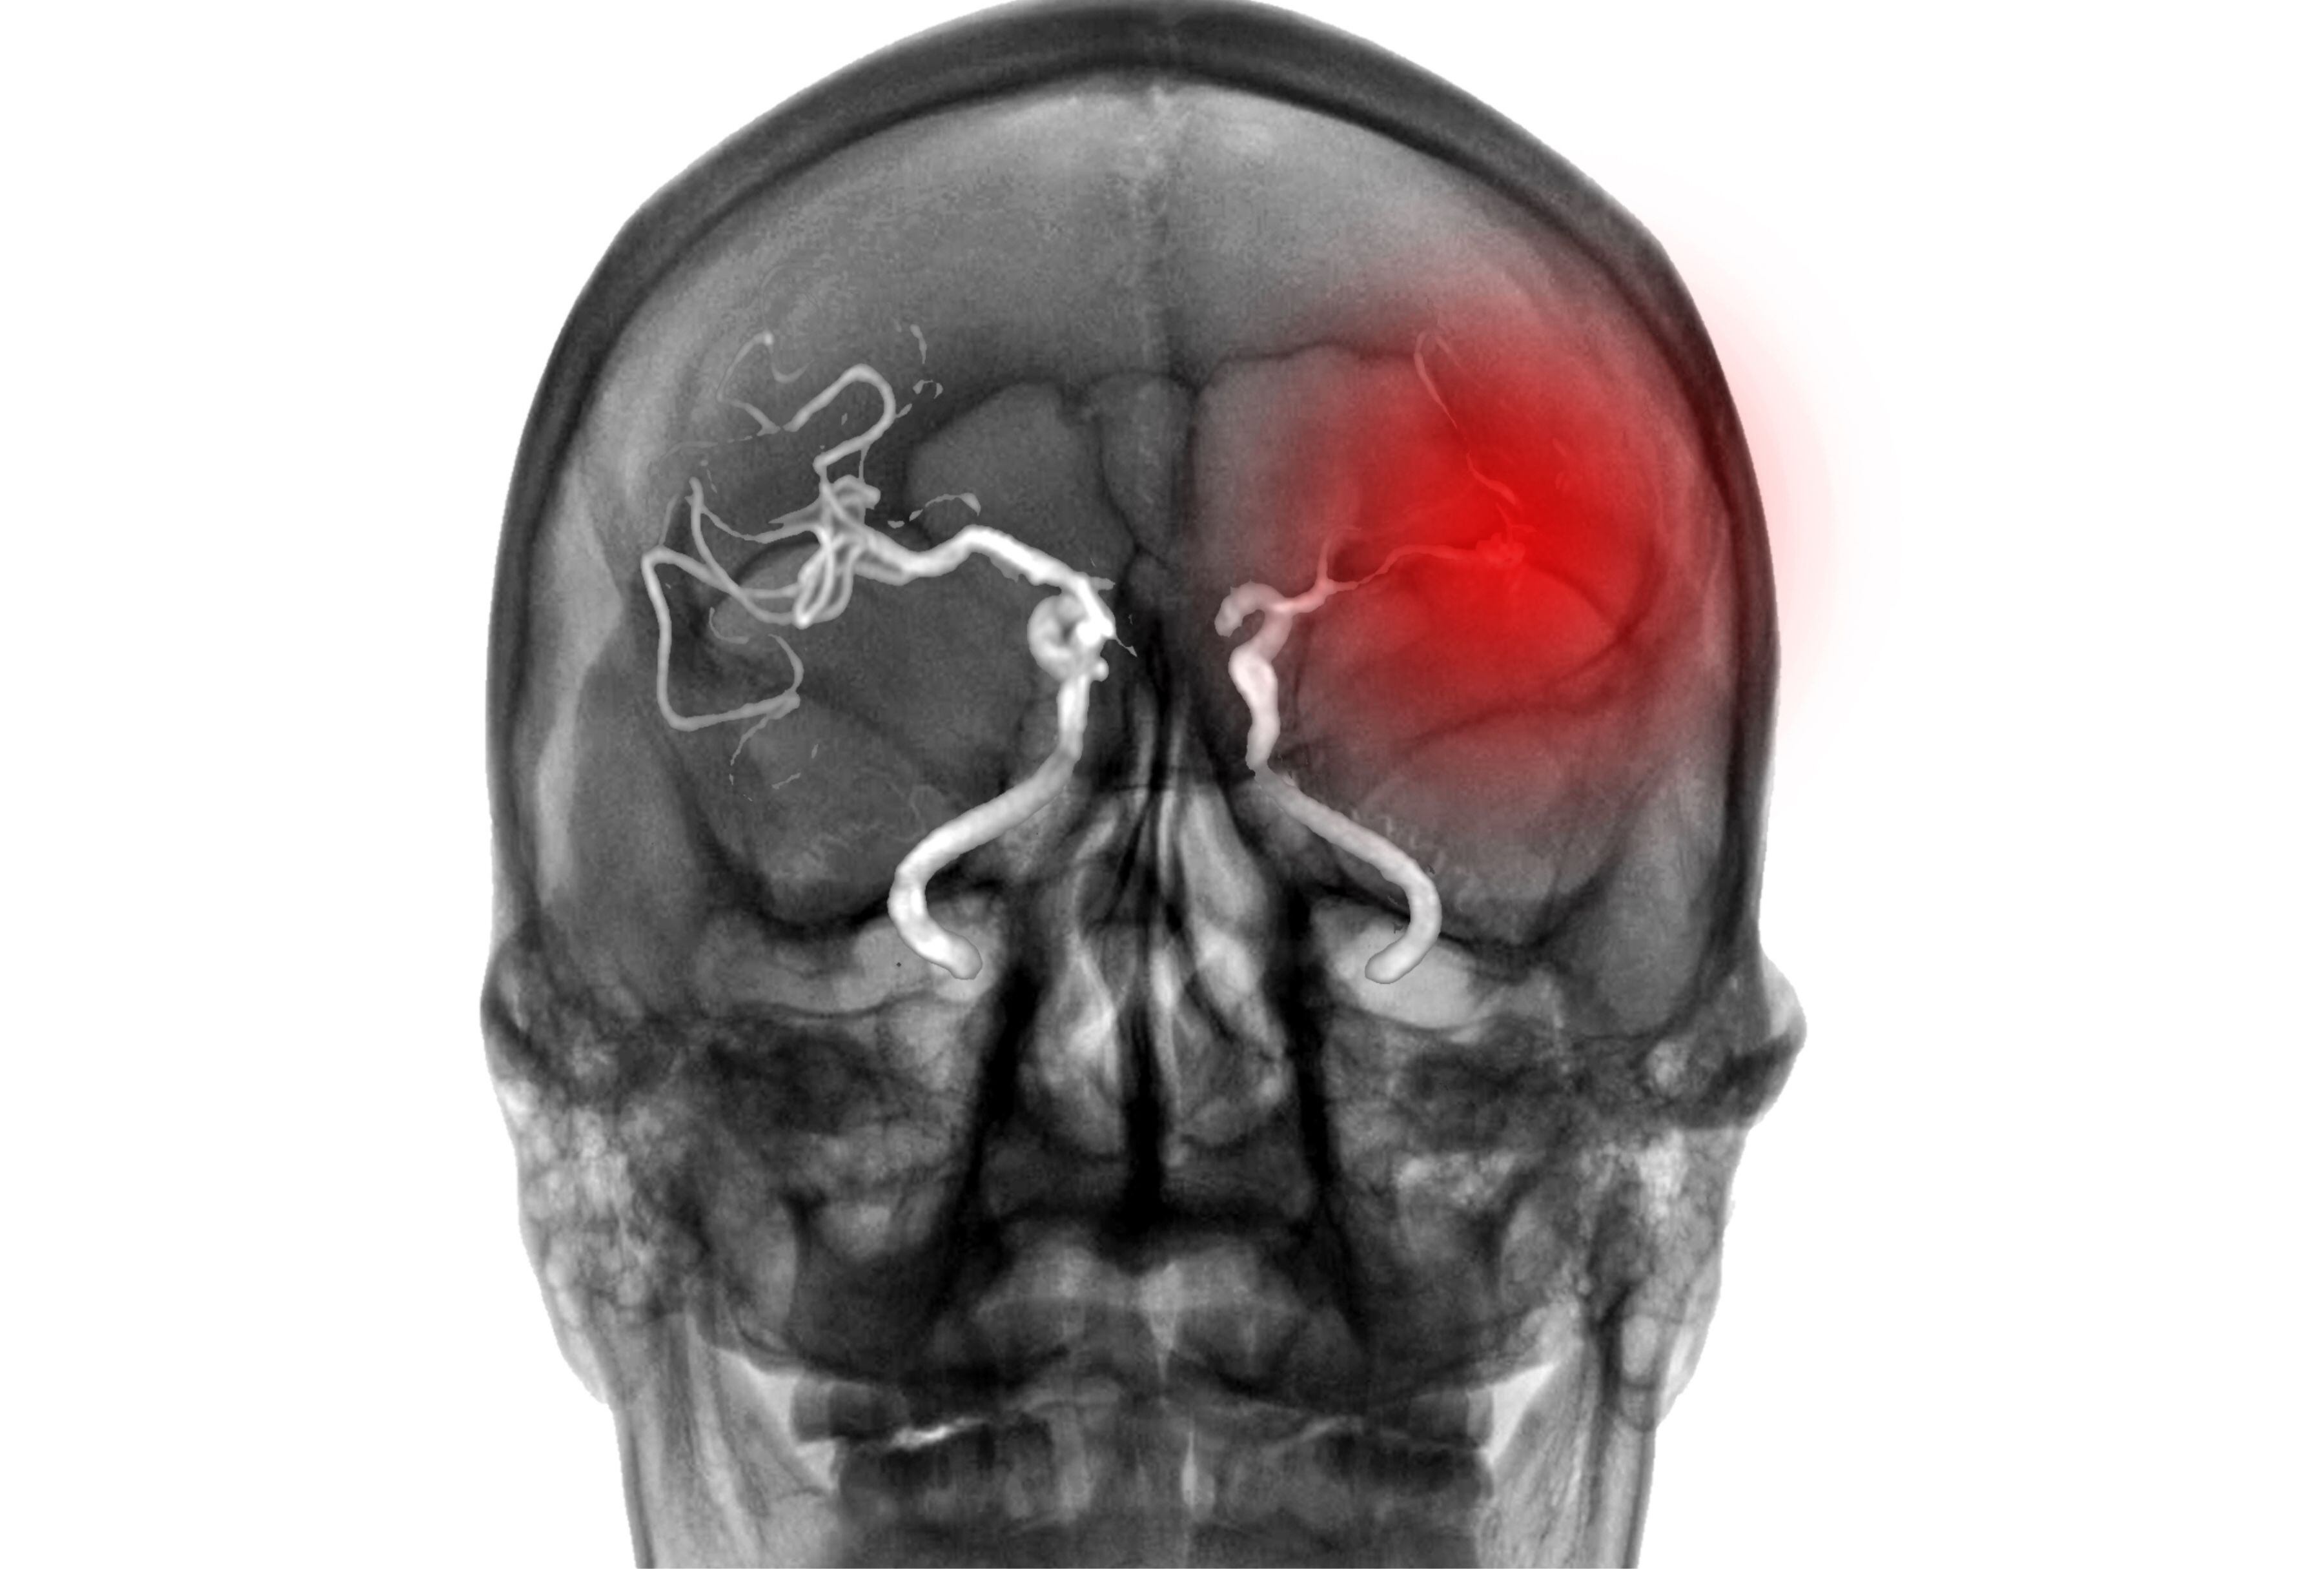

Un estudio sobre la contaminación del aire en The Wasatch Front, una zona de Utah conocida por su pobre calidad del aire, encontró que los pacientes hospitalizados por sangrado en el cerebro habían estado expuestos a niveles altos de aire contaminado.

“Encontramos que estos pacientes estaban experimentando niveles más altos de Ruptura aneurismal tres a seis meses después de altos niveles de polución en el aire”, comentó Robert Rennert, neurocirujano de la mencionada universidad, quien dirigió la investigación de un estudio retrospectivo de 70 pacientes tratados por hemorragia subaracnoidea aneurismática.

El lapso de tiempo entre el momento en que los niveles de PM2.5 alcanzaron su punto máximo y la ocurrencia de la Ruptura aneurismal dificulta el estudio de la asociación entre estos eventos. No obstante, la ruptura aneurismal atípica conlleva un alto riesgo de muerte y discapacidad, por lo que comprender los factores de riesgo en pacientes resulta crucial.

Si bien el estudio no termina de probar una causa y efecto entre los agentes contaminantes y la ruptura aneurismal, los investigadores sospechan que la exposición prolongada a estos contaminantes podría crear múltiples problemas de salud que eventualmente aumentan el riesgo de hemorragias cerebrales. La contaminación atmosférica sensibiliza nuestros cuerpos a las cascadas de citocinas inflamatorias, provoca una acumulación de daño celular y altera los procesos de reparación del ADN.

Rennert y su equipo consideran que este tipo de daño podría acumularse y debilitar los vasos sanguíneos del cerebro, lo que eventualmente provoca rupturas. “Se necesitan futuros estudios sobre cómo la exposición a PM2.5 afecta los cambios inflamatorios locales o a nivel celular para definir mejor esta asociación”, sostuvo el equipo.